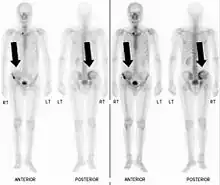

Also known as a bone scan, bone scintigraphy involves the injection of a small amount of radioactive tracer into the bloodstream. This tracer decays and emits radioactive energy which can be detected by a special camera. The camera produces a black and white image where areas shown as dark black indicate bone damage of some kind. If there is a black spot in the lumbar vertebrae (e.g. L5) this indicates damage and potentially spondylolysis. If this test is positive, a CT scan is usually ordered to confirm spondylolysis.[13]

Commonly known as a CT Scan or CAT scan, this form of imaging is very similar to x-ray technology but produces many more images than an x-ray does. The multiple images produce cross-sectional views not possible with an x-ray. This allows a physician or radiologist to examine the images from many more angles than an x-ray allows. For this reason the CT scan is much more accurate in detecting spondylolysis than an x-ray. Bone scintigraphy combined with CT scan is considered the gold standard which means that it is best at detecting spondylolysis.[13][15]